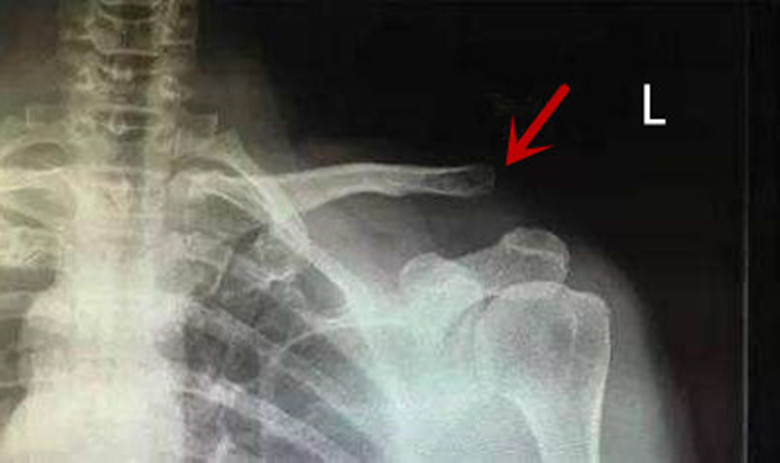

红色箭头标识的部位就是病人所述的“翘起来了”,翘起来的就是锁骨。为了解释清楚这个问题,我先来给大家看一下正常的锁骨没有翘起来是什么样的,也就是说正常的肩锁关节到底是什么样子的,请看下图:

从上图的解剖中大家都应该都能想象出来,肩锁韧带损伤会造成肩锁关节的间隙增宽,这就是一度的肩锁关节脱位。而肩锁韧带合并喙锁韧带的损伤就会造成肩膀翘起来了,损伤越重,翘得越高,最严重的自然是三度脱位。我们来复习这个病人的X线:

这明显就是一个最严重程度的三度肩锁关节脱位,这种程度的肩锁关节脱位后,肩锁韧带和喙锁韧带都已经断裂,断裂后造成分离,韧带不连在一起,因此也长不起来。同时,也没法复位,压下去必然又抬起来,最好的办法就只能是手术了。手术办法也很多,可以是钢板压下去,也可以用钢丝*绑捆**,还可以用丝线拉紧,如下图。